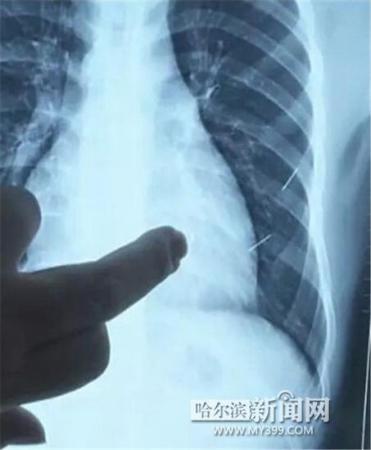

醫(yī)生指出X光片上的針狀物

昨日上午,記者在哈醫(yī)大二院第八住院部心外三病房找到了躺在病床上痛苦不堪的董立仁,家屬正在他身旁不斷安慰著他。見記者前來,董立仁母親李百燕拿出一張X光片,上面可以清晰地看到胸腔內(nèi)一共有4根針狀物,其中一根在心臟部位,兩根在胸腔壁上,還有一根在腹腔壁上。

心外三病房董立仁的主治醫(yī)生告訴記者,董立仁送到醫(yī)院時病情很危險,隨時可能危及生命。“通過檢查發(fā)現(xiàn),他心臟內(nèi)有一個金屬異物,正好在心臟上。心臟每次跳動都與其產(chǎn)生摩擦,導致出血,心包積液懷疑是血液。如果大量出血會凝結(jié)成血塊,血塊包裹住心臟就會影響心臟跳動,隨時都有停跳的危險。心臟上的異物是致命傷,其余胸腔壁和腹腔壁的異物傷害不大?!?/p>

昨天16時30分左右取針手術(shù)開始。因鋼針隨時會危及患者生命,此次手術(shù)定義為大型手術(shù)。開胸后,醫(yī)生打開董立仁心包,發(fā)現(xiàn)一枚鋼針已深深扎入心臟,僅露出1厘米長度在外。拔出鋼針后,醫(yī)生發(fā)現(xiàn),這枚針長達5厘米。受鋼針影響,心包出現(xiàn)大量積液,近800毫升。

隨后,在下胸壁位置,第二枚鋼針順利取出。在尋找另兩枚鋼針過程中,普外、胸外多名醫(yī)生也參與手術(shù),為主刀醫(yī)生提供更為穩(wěn)妥的處理建議。根據(jù)X光片顯示位置,醫(yī)生未在患者體內(nèi)找到剩余兩枚鋼針。醫(yī)生懷疑,其中一枚鋼針可能深藏在肋骨骨膜位置,無法尋找,最后決定結(jié)束手術(shù),做進一步觀察,研究下一次手術(shù)方案。